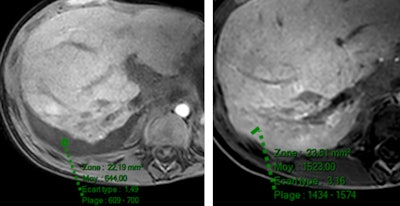

Two radiologist readers interpreted the scans qualitatively and quantitatively on precontrast, dynamic, and hepatobiliary phases. Qualitatively, fluid was described as hypointense in the hepatobiliary phase with Primovist, while it was hyperintense with MultiHance. When quantitatively measured, fluid signal intensity increased with both MultiHance and Primovist, but it was significantly more marked after MultiHance.

"Within the four groups we looked at what happened in the hepatobiliary phase. Nearly all the patients injected with MultiHance had iso- or hypersignal intensity of the fluid, but this was not true of those injected with Primovist," Ronot told AuntMinnieEurope.com ahead of the meeting.

Ronot believed the key lay in the time delay between injection and acquisition. With Primovist, the time delay is usually 20 minutes, but with MultiHance it is 1.5 to two hours, allowing more time for contrast agent accumulation in the fluids.

"If you inject hepatospecific contrast agents there will be some degree of fluid enhancement but this is generally not seen with Primovist because the time from injection to image acquisition is too short. Time to acquisition with MultiHance on the other hand is long enough to see the enhancement," Ronot said.